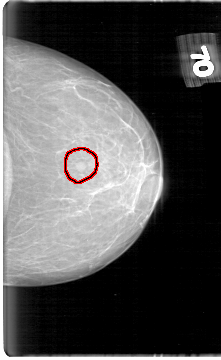

D_4060_1.LEFT_CC

LEFT_CC LINES 5386 PIXELS_PER_LINE 3301 BITS_PER_PIXEL 12 RESOLUTION 43.5 OVERLAY

FILE: D_4060_1.LEFT_CC.OVERLAY

TOTAL_ABNORMALITIES 1

ABNORMALITY 1

LESION_TYPE MASS SHAPE ROUND MARGINS OBSCURED

ASSESSMENT 0

SUBTLETY 4

PATHOLOGY BENIGN

TOTAL_OUTLINES 1

BOUNDARY